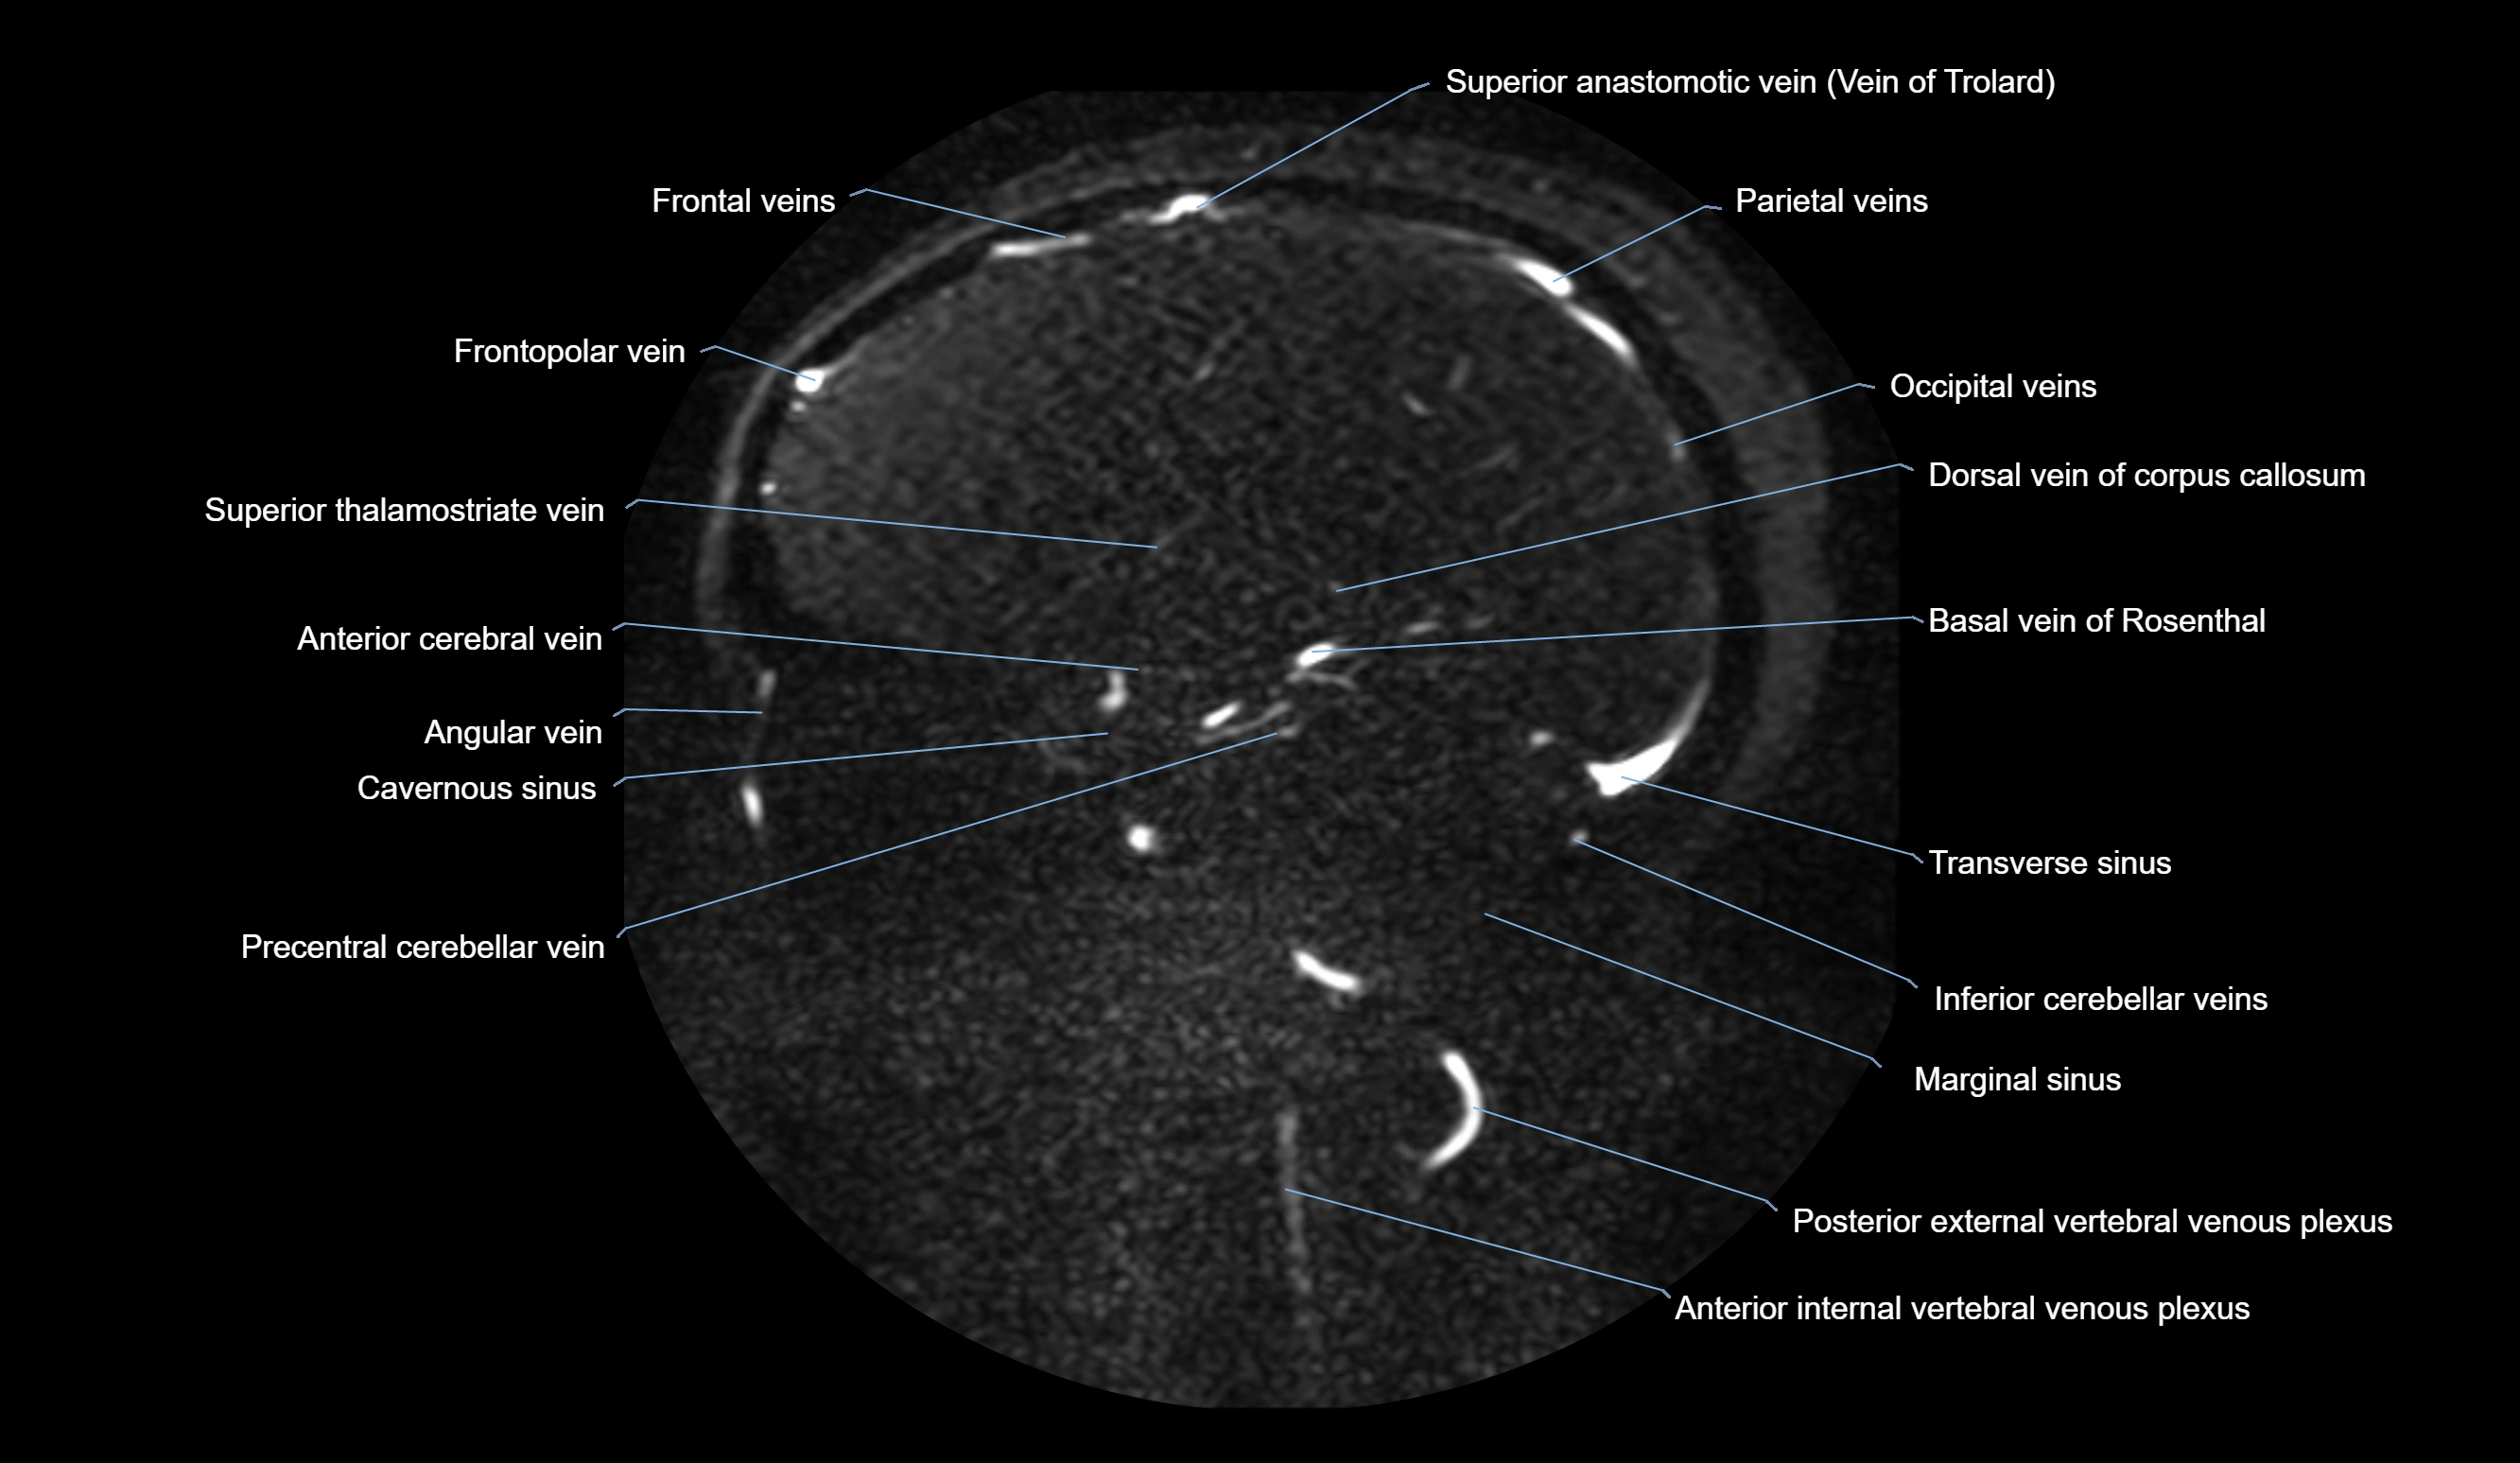

MR Venography (MRV):

• Time-of-flight (TOF) or contrast-enhanced MRV shows the angular vein as a bright enhancing venous channel

• Clearly demonstrates its continuity with the facial vein and superior ophthalmic vein

• MRV is highly useful in evaluating thrombosis, venous obstruction, or collateral venous drainage

MRI images